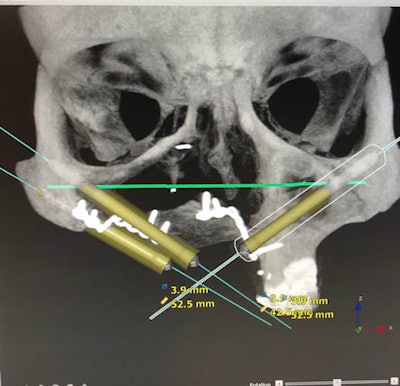

Three months later, magnetic resonance imaging and positron emission tomography imaging confirmed no tumor recurrence. Using implant planning software and a combination of virtual modeling and a 3D-printed replica of the maxilla, three zygomatic implants and two regular implants were proposed. Even with jaw stretching exercises, surgical access for implant placement was difficult, particularly with the limited bone on the right side.

Thirteen months after the initial surgery, implants were placed into the right infraorbital rim, the right zygoma, and the left zygoma. Impressions were taken two days later, and Taylor was fitted with a screw-retained resin provisional bridge.